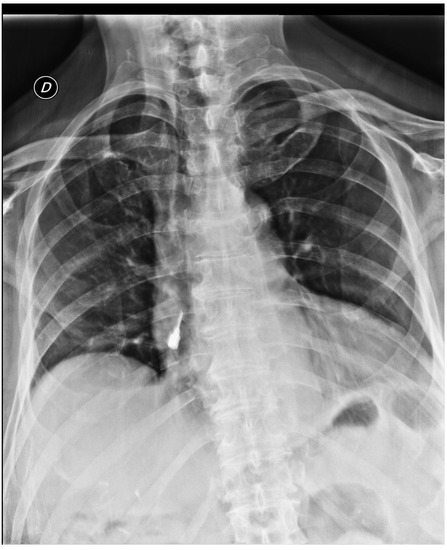

Although the patient had no complaints, he was admitted to the Accident & Emergency Department (A&E) and underwent a thorax and abdomen radiograph. It disclosed the presence of a “radiopaque foreign body projecting on the right cardiac atrium” (Figure 3 and Figure 4) and the radiologist diagnosed the presence of a screwdriver in the distal esophagus. Subsequently, the patient was referred to the endoscopy unit to undergo an upper GI endoscopy with the aim of retrieving the foreign body. During the first phase of sedation, when the patient was lying in a recumbent position, he began to cough; so he was immediately placed in the classical left lateral position and he suddenly stopped coughing. The gastroenterologist performed the study thoroughly, by viewing the esophagus, stomach, and the second part of the duodenum very carefully. However, no object was found. Nevertheless, a very tortuous esophagus with absent motility and presence of varix in the upper portion was revealed, as well as a large diverticulum filled with food mixed with bile in the second part of the duodenum. The gastroenterologist carefully washed the second part of the duodenum but the screwdriver was not found. After this unsuccessful procedure, it was unclear whether the screwdriver had already passed beyond the second part of the duodenum or there was a misinterpretation of the previous radiograph.

Figure 3. Front view of the thorax and abdomen radiograph.

Figure 4. Lateral view of the thorax and abdomen radiograph.